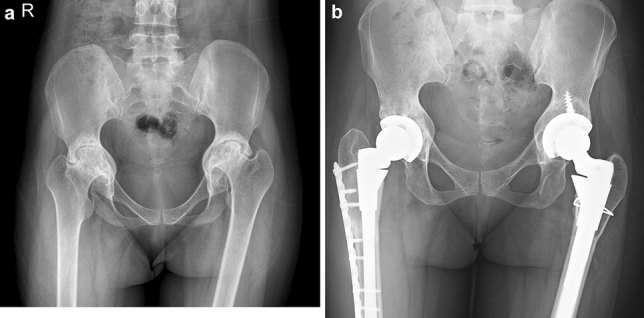

42 (50%) of the patients studied had bilateral fused hips (Fig. 2). Eleven (13%) patients had a fused hip on one side, while the other hip had limited flexion (range 20°–70°) that was painful. The remaining 31 (37%) patients had some pre-operative movement in both hips (range 20°–80° of flexion), but as both hips were painful and caused significant functional disability, bilateral hip replacement was performed. 29 (34%) patients had a fixed flexion deformity of > 30°, of which 15 (51%) had a flexion deformity of > 50°. The mean range of pre-operative hip flexion was 32°, while post-operative hip flexion was 92° (range 45–110).

Fig. 2.

Pre-operative AP view (a) and Post-operative AP view (b) radiographs of a patient with bilateral ankylosis of the hips, who underwent an uncemented bilateral total hip replacement